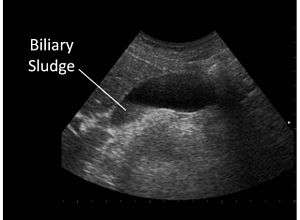

Biliary sludge

Biliary sludge in gallbladder on ultrasound | |

Biliary sludge refers to a viscous mixture of small particles derived from bile.[1][2] These sediments consist of cholesterol crystals, calcium salts, calcium bilirubinate, mucin, and other materials.[1][2][3]

Biliary sludge is typically diagnosed by CT scan, transabdominal ultrasonography.[1][2] Endoscopic ultrasonography is another more sensitive option. However, the gold standard is considered to be direct microscopy of aspirated gallbladder bile.[1][2] This method is much more sensitive, although it is less practical.[2]